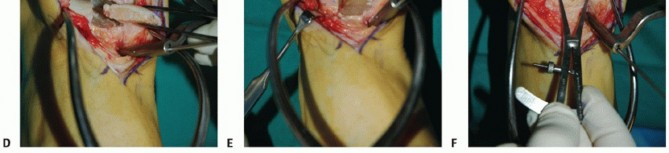

It is unlikely that a perfect clinical and fluoroscopic match will be achieved. Attempt to achieve the best clinical match of the graft's articular surface with the surrounding native cartilage (TECH FIG 4A).

Graft fixation

Ideally, the graft will have some interference fit.

We routinely secure the graft with one or two small-diameter solid screws (1.5 or 2.0 mm in diameter). One is typically placed from dorsal to plantar and the other from medial to lateral (if the depth of the graft will allow) (TECH FIG 4B,C).

Place the screws in lag fashion.

Countersink the screw heads below the articular surface (TECH FIG 4D,E).

Using fluoroscopy, confirm that the graft and hardware are in optimal position (TECH FIG 4F-H).

The graft will not look perfect fluoroscopically, but as long as the clinical appearance is acceptable, the outcome has a good chance to be favorable.

The hardware may appear slightly proud fluoroscopically despite being countersunk. The talar dome is not a flat plane, and therefore the screw may seem to be protruding. Moreover, the articular cartilage is rather thick compared to such a low-profile screw head.

- TECH FIG 4 • A-C. Fitting and securing the graft to the native talus. A. After contouring the graft (some minor discoloration from debris while manipulating graft on back table; it is easily washed away). B. Drill hole perpendicular to graft. C. Securing graft with two countersunk screws. (continued)

Fixation of the graft to the native talus (TECH FIG 9C-G)

We routinely use two solid small-diameter screws (1.5 or 2.0 mm) placed in lag fashion to secure the graft to the native talus.

These are placed anteriorly and countersunk below the articular surface, typically anterior to the tibial plafond with the ankle in neutral position.

Although we would prefer to avoid violating the cartilage surface, to date, we are not aware of any compromised outcome related to the articular defect created by placing the screws.

Because the talus is contained within the ankle mortise, in our experience, posterior screw fixation is unnecessary.

We routinely assess graft position after screw placement fluoroscopically. Because the articular cartilage is not visible and the physiologic talar dome is not in a single plane, the countersunk screws may appear proud fluoroscopically. - Axial Realignment